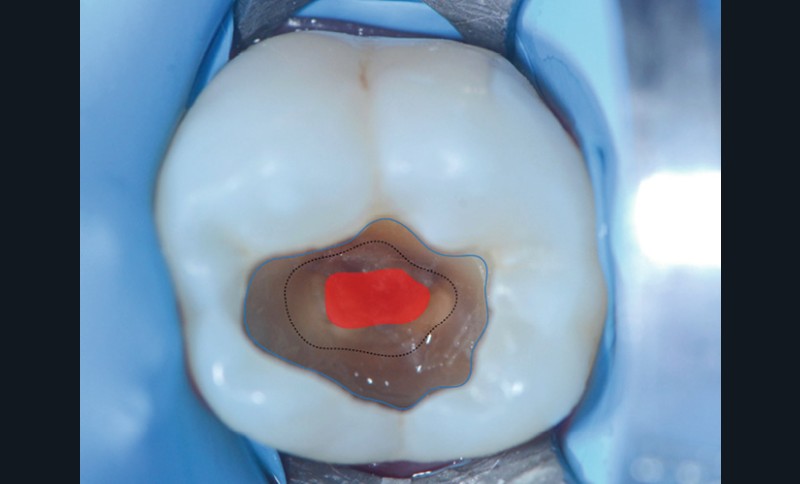

Le curetage total consiste à éliminer l’ensemble de la dentine cliniquement altérée (dentine nécrosée, infectée et affectée (fig. 1)) jusqu’à l’obtention d’un fond de cavité dur et visuellement sain (fig. 2). Cette approche repose sur un objectif clair : réduire au maximum la charge bactérienne et offrir un fond de cavité permettant un collage idéal. Dans les lésions profondes, elle expose toutefois à un risque d’effraction pulpaire [2] (fig. 3). Ce risque est aujourd’hui mieux accepté grâce aux progrès des biomatériaux de coiffage pulpaire, notamment les silicates de calcium (fig. 4), qui permettent une cicatrisation pulpaire prédictible lorsque le diagnostic est favorable, le protocole rigoureux et l’hémostase contrôlée. En cas d’effraction pulpaire, cette technique permet en outre l’évaluation visuelle directe de la pulpe (aspect, couleur, saignement). Le protocole clinique impose d’être sous champ opératoire et nécessite un plateau technique adapté.